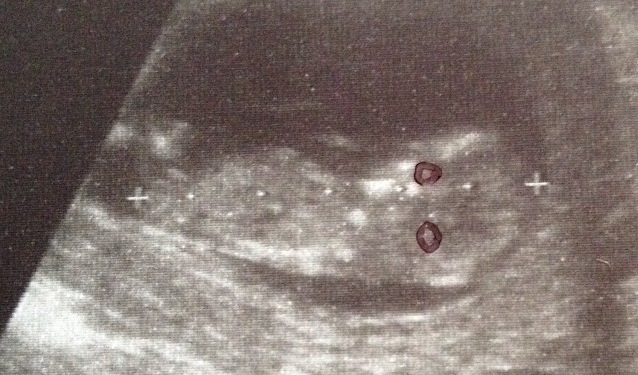

Attachment 15877

18 wks 2 days